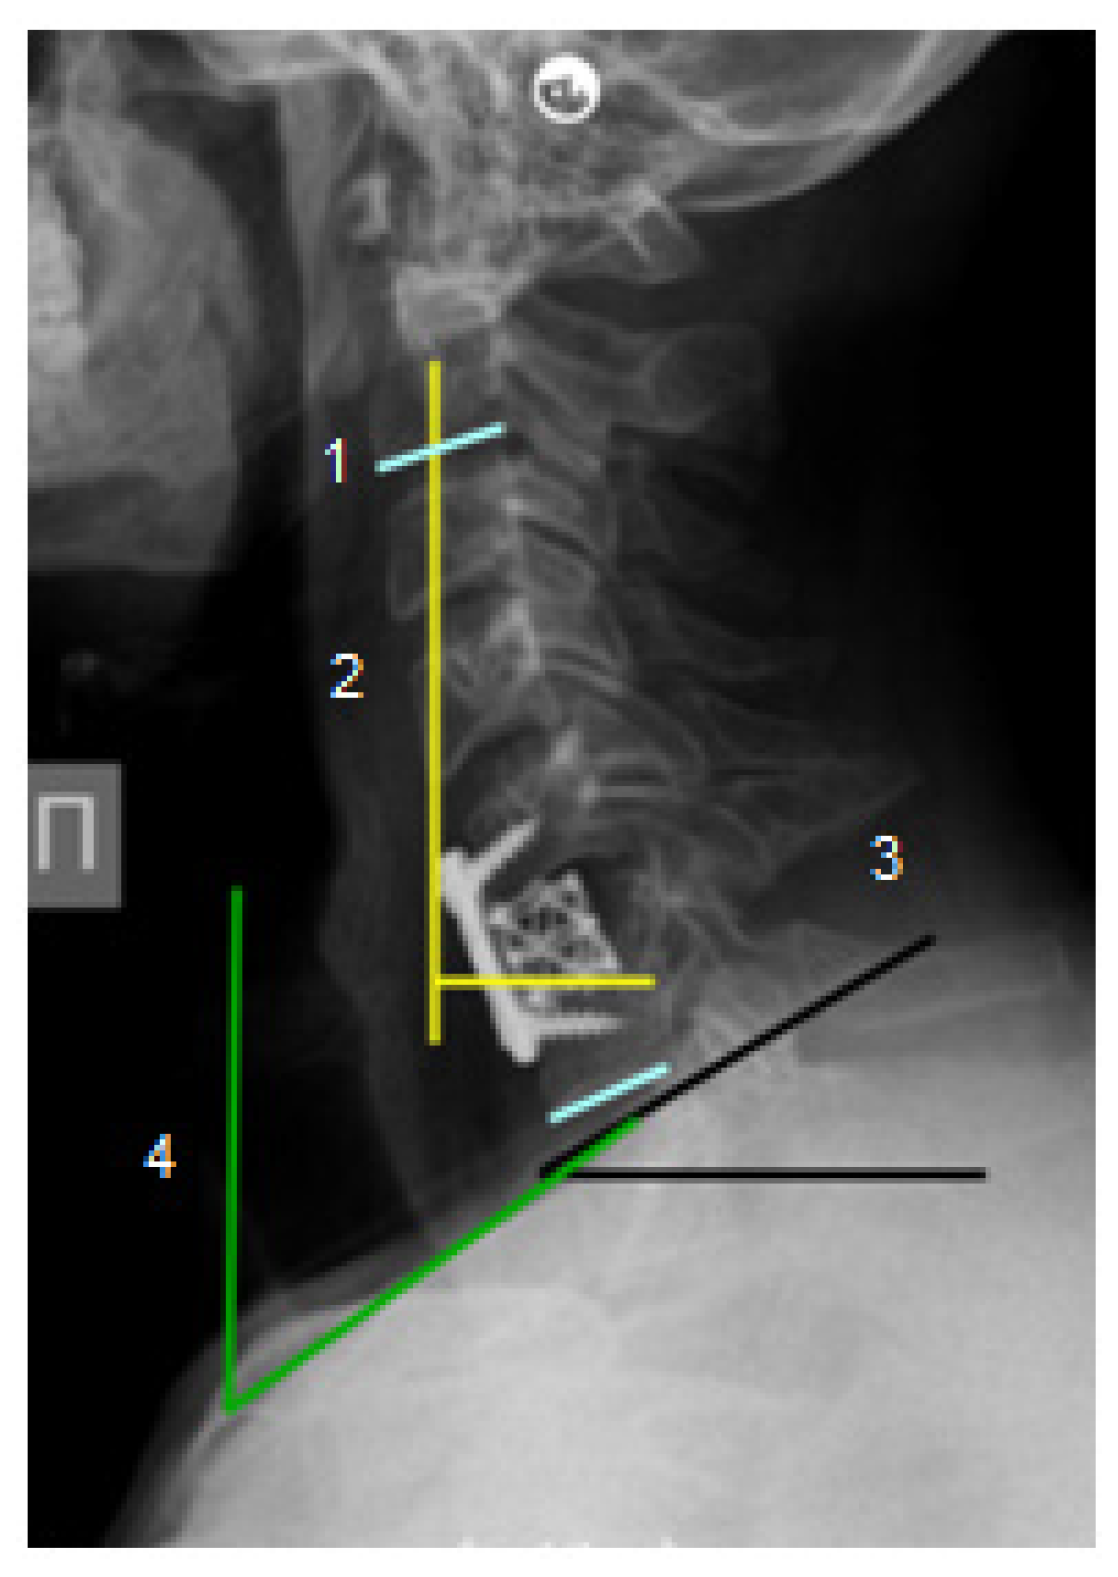

Neurological status was studied according to the Frankel scale [19] before surgery and at the time of hospital discharge. Follow-up was at 38 ± 4 months (mean: 3 years, 3 months). All patients underwent preoperative radiological examination, including cervical spine radiography in the lateral projection, computed tomography to determine the extent of bone destruction, and magnetic resonance imaging to assess intramedullary changes and the presence of epidural, para- and prevertebral abscesses. Sagittal balance parameters were evaluated by radiography: CSVA with the delineation of reference values for sagittal imbalance >4 cm, Th1 slope (>25°) and NTA (range limits 13° to 25°) [20]. Calculations were performed using Surgimap v2.3.2.1 software (Methuen, MA, USA) with the preliminary anonymization of data (Figure 1).

Figure 1.

Cervical spine radiograph in the lateral projection in a patient with infectious cervical spondylitis. Symbols: 1—cervical lordosis C2-C7; 2—cervical sagittal vertical axis (CSVA); 3—Th1 slope (T1S); 4—neck tilt angle (NTA).